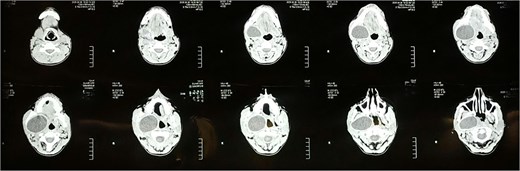

Fine-needle aspiration cytology suggested a benign cystic lesion. Contrast-enhanced computed tomography (CT) of the neck showed a 67 × 38 × 53 mm well-defined cystic mass occupying the right parapharyngeal space, extending from the mandibular condyle in the prestyloid compartment to the mandibular angle (Fig. 1). No daughter cysts, calcifications, or ‘water-lily’ signs were noted.

Axial cuts of CT scan showing a well-defined cystic lesion occupying the right parapharyngeal space.